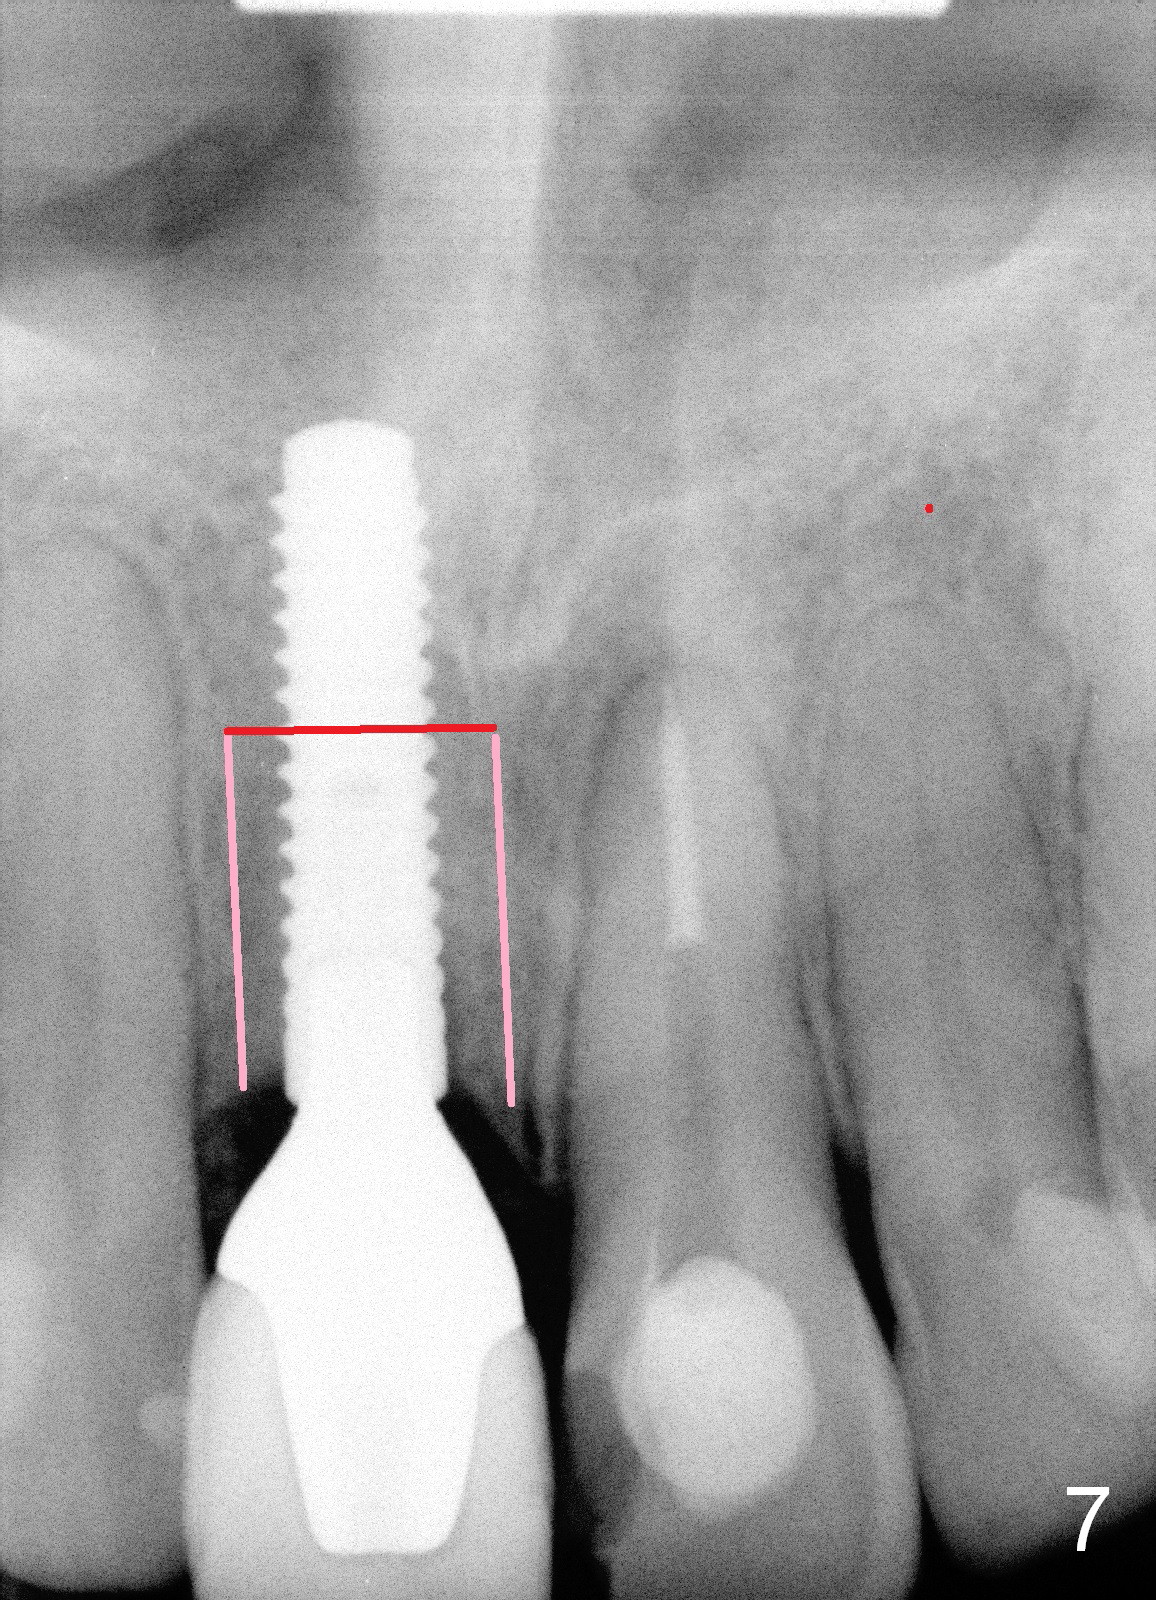

If segmental osteotomy is the only option, the transverse cut may be through the implant (Fig.7). There will be stable fixation (Fig.8).